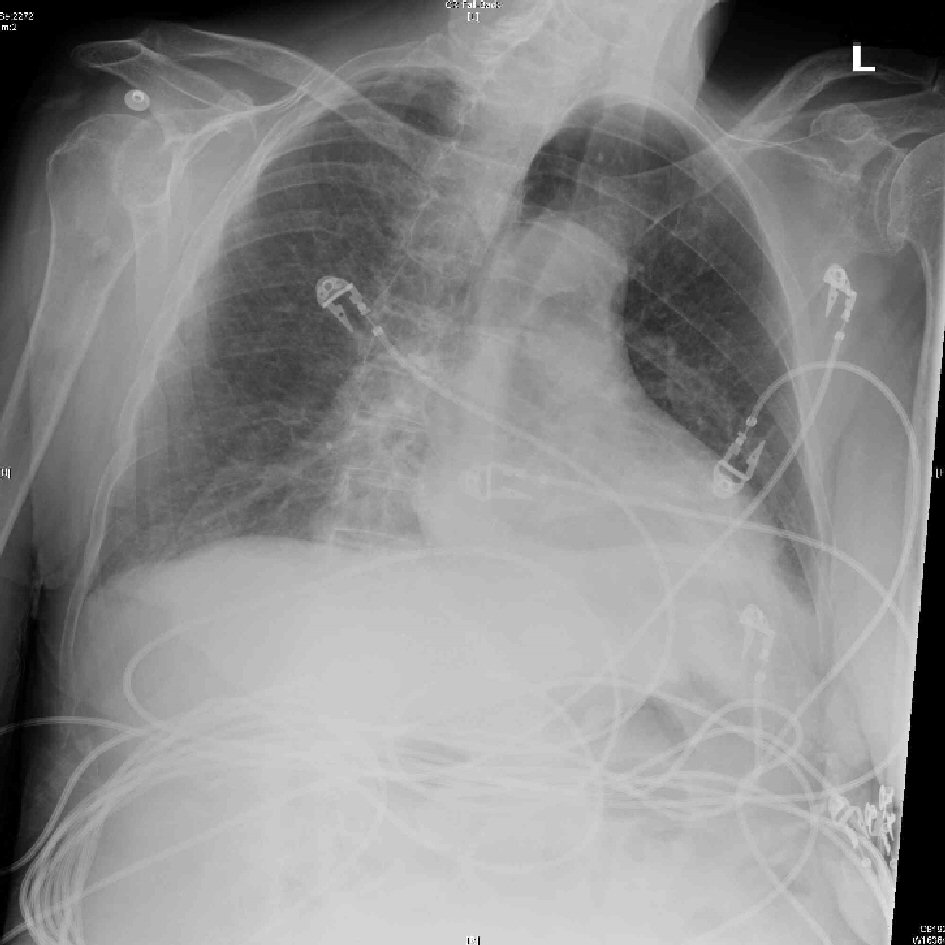

Unlike the aforementioned expected findings, this case was characterized by severe hypokalemia, metabolic alkalosis, low normal glucose and normal cortisol. There was no pleural effusion or cardiomegaly on chest radiograph (Fig. 4). Serum troponin was 0.01 ng/mL and electrocardiogram (ECG) (Fig. 2) did not show signs of cardiac ischemia. Notably, hyponatremia was absent. Generally, myxedema coma results from several years of untreated hypothyroidism, and it carries a greater mortality than 50% [4]. In this case, the family stated that her symptoms of lethargy and medical non-compliance with levothyroxine started about 6 months ago. Although a respiratory acidosis was expected due to her chronic regimen of morphine extended-release 15 mg, arterial blood gas (Table 1) on admission showed pH of 7.63, PaCO2 of 39.6 mm Hg, PaO2 of 56 mm Hg and a bicarbonate of 41.9 mmol/L, reflecting a primary metabolic alkalosis without respiratory compensation. In addition to severe hypokalemia of 2.0 mmol/L and hypochloremia of 78 mmol/L, metabolic alkalosis was thought to be due to contraction alkalosis from dehydration relating to lack of oral hydration. The patient was not on diuretic therapy. Hypochloremia, caused by chloride loss from the gut, kidney, skin, or in this case, decreased oral intake results in alkalosis because bicarbonate generated during the production of gastric acid returns to the circulation leading to net accumulation of base with net loss of acid from the extracellular fluid (ECF) [7]. Hypokalemia augments the alkalosis by causing an intracellular shift of hydrogen, thus increasing ECF bicarbonate concentrations and potassium depletion independently augments bicarbonate reabsorption in the proximal tubule [7]. Contraction alkalosis, defined as acute decrease in ECF [8], further maintains alkalosis by increased fluid reabsorption in the proximal tubule where bicarbonate is preferentially reabsorbed compared with chloride [7].

![]() Click for large image | Figure 4. No pleural effusion or cardiomegaly on chest X-ray. |